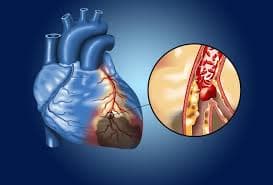

Antes de mais nada, o Tratamento para Doença Arterial Coronária reduz riscos cardíacos ao controlar placas nas artérias e melhorar a circulação do sangue no coração.Além […]

Antes de mais nada, o Tratamento para Angina exige diagnóstico rápido, avaliação cardiológica detalhada e estratégias terapêuticas que aliviam a dor no peito.Além disso, acompanhamento contínuo […]

Antes de mais nada, o Tratamento de Infarto exige atendimento rápido, equipe especializada e condutas médicas imediatas para preservar o músculo cardíaco.Além disso, ação ágil reduz […]

Antes de mais nada, Infarto do Miocárdio ocorre quando o fluxo de sangue para o coração diminui ou bloqueia totalmente, causando lesão no músculo cardíaco.Além disso, […]

Antes de mais nada, Doença Arterial Coronária representa uma das principais causas de infarto e morte cardiovascular no Brasil, exigindo diagnóstico rápido e acompanhamento especializado.Além disso, […]